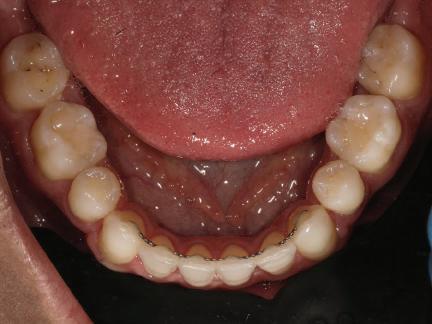

20 Dental Tribune Bulgarian Edition / октомври 2022 г. П ациентите със завършен растеж и скелетни проблеми обикновено представляват предизвикателство за ортодонт ската практика. Необходимостта от изваждане на зъби в комбинация с особеностите на възрастовата ортодонтия изисква особено внима ние. Фокусът върху критично важното значение на позицията на долните резци във връзка с дългосроч ната стабилност и постигането на оптимални оклузални взаимоотношения при затварянето на екстракционните пространства лесно може да излезе извън контрол. Когато към тези чисто кли нични проблеми се добави и стресът от натоваре ната практика, предизвикателството става още по-голямо. Всички тези фактори налагат използ ването на доказан подход с ясни и последовател ни стъпки, в което се разкрива силата на дисциплината „Алекзандър“ – предвидим протокол през целия процес на елиминиране на ротациите, ниве лиране на дъгите, затваряне на екстракционните пространства и финализиране на случая. Именно такъв е и случаят, който презентираме –екстракционен, скелетен клас 3 при възрастен па циент, лекуван по системата „Алекзандър“. ПРЕДВИДИМИ РЕЗУЛТАТИ ПРИ ПАЦИЕНТИ СЪС ЗАВЪРШЕН РАСТЕЖ И СКЕЛЕТЕН КЛАС 3, ИЗПОЛЗВАЙКИ ЕКСТРАКЦИОННО ЛЕЧЕНИЕ ПО ДИСЦИПЛИНАТА „АЛЕКЗАНДЪР“ Д-р Радой Димитров, България Преди започване на лечение клиничен случай | ортодонтия Фиг. 1а–1e Преди започване на лечение. Пациентът пристига в практиката с основното оплакване от невъзмож ност за нормално дъвчене. Снета е цялата необходима диагностична ин формация. Фиг. 1f–1h Снимки в профил и анфас. Фиг. 1i–1k Панорамна снимка, телерентгенография и анализ на телерент генография. Фиг. 1а Фиг. 1d Фиг. 1f Фиг. 1g Фиг. 1h Фиг. 1e Фиг. 1b Фиг. 1c Фиг. 1i Фиг. 1j Фиг. 1k

closed.

21Dental Tribune Bulgarian Edition / октомври 2022 г. ДИАГНОСТИЧНИ РЕЗУЛТАТИ: 1. Възраст на пациента: 21 години 2. Скелетен клас III (ANB 0) 3. Зъбен клас 3 4. Ръбцова захапка във фронта, кръстосана в дисталните участъци 5. Тясна горна челюст 6. Overjet – 0 мм, Overbite – 0 мм 7. Несъответствие на горната с долната средна линия 8. Единични контакти в ЦО 9. Хиподивергентен тип на растеж SN/MP – 33.5 10. Неравен гингивален контур 11. Неравна линия на усмивката 12. Тенденция за рецесии в долен фронт ПРЕПОРЪЧИТЕЛНО ЛЕЧЕНИЕ: Пълно ортодонтско лечение с метални брекети „Алекзандър“ Корекция на клас 3 захапката в областта на кучешките зъби с екстракция на първите пре молари в долна челюст Корекция на кръстосаната захапка в дистални участъци Коригиране на ръбцовата захапка във фронта Подобряване на ОJ и OB на пациента Стрипинг в долен фронт Подреждане на зъбите в горната и долната челюст Професионално хигиенизиране и профилактични дентални прегледи са препоръчителни на всеки 6 месеца. 1-ви месец След 1 месец са залепени брекети в горната челюст – поставена е еластична дъга. 016 NiTi. В долната челюст са елиминирани ротациите, поставена е стоманена дъга. 016SS, закалена с ток, и еластична верижка за затваряне на пространствата. 3-ти месец В долната челюст е поставена трета дъга – 17 x 25 NiTi с къси лигатури и верижка

В горната челюст се затварят пространствата с дъга .016SS и верижка. 5-и месец На 5-ия месец след залепяне на брекетите в долната челюст е поставена стоманена дъга 16 x 22 SS с четвъртито сечение, омега луп и тай бек. В горната челюст е поставена дъга 17 x 25 NiTi. Поради липсата на стабилни оклузални контакти са поставени лингвални верижки в областта на моларите, за да се предотврати нежелана ротация на 7-ите зъби. 6-и месец На 6-ия месец от началото на лечението са екстрахирани долните първи премолари, поставена е дъга 16 x 22 SS със затваряща чупка teardrop. Чупката се активира всеки месец по 1 мм с чинч-бек. клиничен случай | ортодонтия СТЪПКИ НА ЛЕЧЕНИЕТО Начало на лечението Лечението започва с поставяне на апарат за бърза експанзия в горната челюст. През първия месец от лечението са направени 24 оборота на апарата за експанзия. Залепени са брекети в долната челюст, поставена е дъга 17x25 CuNiTi, като са предпи сани клас 3 ластици (1/4”,4 1/2 oz) по време на сън, за да се осигури контрол върху торка на долните резци. Фиг. 2а Фиг. 3a Фиг. 4a Фиг. 3b Фиг. 4b Фиг. 3c Фиг. 4c Фиг. 3d Фиг. 4d Фиг. 3e Фиг. 4e Фиг. 5a Фиг. 5b Фиг. 5c Фиг. 5d Фиг. 5e Фиг. 6a Фиг. 6b Фиг. 6c Фиг. 6d Фиг. 6e Фиг. 7a Фиг. 7b Фиг. 7c Фиг. 7d Фиг. 7e Фиг. 2b Фиг. 2c Фиг. 2d

Dental Tribune Bulgarian Edition / октомври 2022 г.22 клиничен случай | ортодонтия 14-и месец В горната и долната челюст са поставени последни стоманени дъга с омега луп и тай бек – 17 x 25 SS с четвъртито сечение. Назначени е ластик за средната линия в комбинация с клас 3 ластик (1/4”, 6 1/2 oz). Контролни рентгенографии 13-и месец Екстракционните пространства са затворени. Направена е контролна панорамна снимка за оценка позицията на корените. Взето е решение за презалепване на брекетите на 12, 22 и пръстените на 36 и 46. 21-ви месец Средната линия в горната и долната челюст съвпадат. Ластиците са спрени. Свалени са пръстените и брекетите в горната и долната челюст, зигзаг ластици не са използвани поради благоприятните оклузални взаимоотношения. Фиг. 11j Ортопантомография в края на лечението. Фиг. 11k Телерентгенография след края на лечението. Фиг. 11l Анализ на телерентгенографията след лечението. Фиг. 11m Последователност на дъгите в горната и долната челюст Фиг. 11n Суперимпозиция на PreOp и PostOp ортопантомографии. 10-и месец Затварянето на пространствата е предвидимо и контролирано, без да се отварят пространства в зъбната дъга. Фиг. 8a Фиг. 8b Фиг. 8c Фиг. 8d Фиг. 8e Фиг. 10a Фиг. 10b Фиг. 10c Фиг. 10d Фиг. 10e Фиг. 9a Фиг. 9b Фиг. 9c Фиг. 9d Фиг. 9e Фиг. 9f Фиг. 11a Фиг. 11f Фиг. 11j Фиг. 11l Фиг. 11m Фиг. 11n Фиг. 11k Фиг. 11g Фиг. 11h Фиг. 11i Фиг. 11b Фиг. 11c Фиг. 11d Фиг. 11e

Dental Tribune Bulgarian Edition / октомври 2022 г. 23клиничен случай | ортодонтия реклама Лечението е продължило 21 месеца. Проведено е домашно избелване с индивидуални шини. За автора: Д-р Радой Димитров завършва с отличие Факултета по дентална медицина към МУ–София през 2015 г. В продължение на 5 години работи в няколко водещи практики в София, като през 2019 г. заедно със своята съпру га д-р Траяна Димитрова основават собствена практика в гр. Гоце Делчев –Dimitrovi Dental Care. Посещава редица курсове за повишаване на квалификаци ята, но най-сериозен тласък в развитието на ортодонтската си практика получава след завършването на комплексната ортодонтска програма, воде на от д-р Иван Горялов, базирана на дисциплината „Алекзандър“ – система с повече от 50 години опит в целия свят. Д-р Димитров е член на Българския изследователски клуб „Алекзандър“. Взе ма участие като гост-лектор в симпозиума с международно участие The Power of the Alexander Discipline, който се проведе на 14–15.05.2022 г. С д-р Ди митров можете да свържете на тел. +359885 252 025. Заключение Представеният случай е ярък пример за възможностите и красо тата на дисциплината „Алекзандър“ – приложен е утвърден под ход с ясни правила и са постигнати очакваните цели. Резулта тът ще бъде дългосрочно стабилен, тъй като са спазени всички правила, които се отнасят към максимално комфортната пози ция на зъбите в края на лечението. Постигнати са красива усмив ка и стабилна оклузия. ПОСТИГНАТИ РЕЗУЛТАТИ ОТ ЛЕЧЕНИЕТО 1. Коригирана ръбцова захапка 2. Коригирана клас 3 захапка в областта на ку чешките зъби 3. Коригирана кръстосана захапка в дисталните участъци 4. Коригиран овърджет и овърбайт 5. Разширена е горната зъбна дъга 6. Подредени зъби в горната и долната челюст 7. Постигната е стабилна захапка с множество контакти в ЦО 8. Драматично е подобрена дъвкателната функ ция 9. Подобрена е линията на усмивката ДРУГИ ПРОВЕДЕНИ ДЕНТАЛНИ ПРОЦЕДУРИ 1. Домашно избелване на зъбите 2. Екстракция на мъдреците Фиг. 12a Фиг. 12b Фиг. 12c Фиг. 12eФиг. 12d Фиг. 12f Фиг. 12g Информация за дати, цени и отстъпки www.bracescourses.com 0889 22 55 01 Практически курсове лектор д-р Иван Горялов Дисциплината „Алекзандър“ ПЪТЯТ КЪМ СУПЕРУСМИВКИТЕ 100% връщане на цялата сума, ако не сте удовлетворени след преминаване на Ниво 1 Директно и индиректно залепяне на брекети Анализ, диагноза и план на лечение Лечение на клас 2 дълбока захапка Екстракционно лечение Лечение на клас 3 отворена захапка НИВО 5НИВО 1 НИВО 2 НИВО 3 НИВО 4